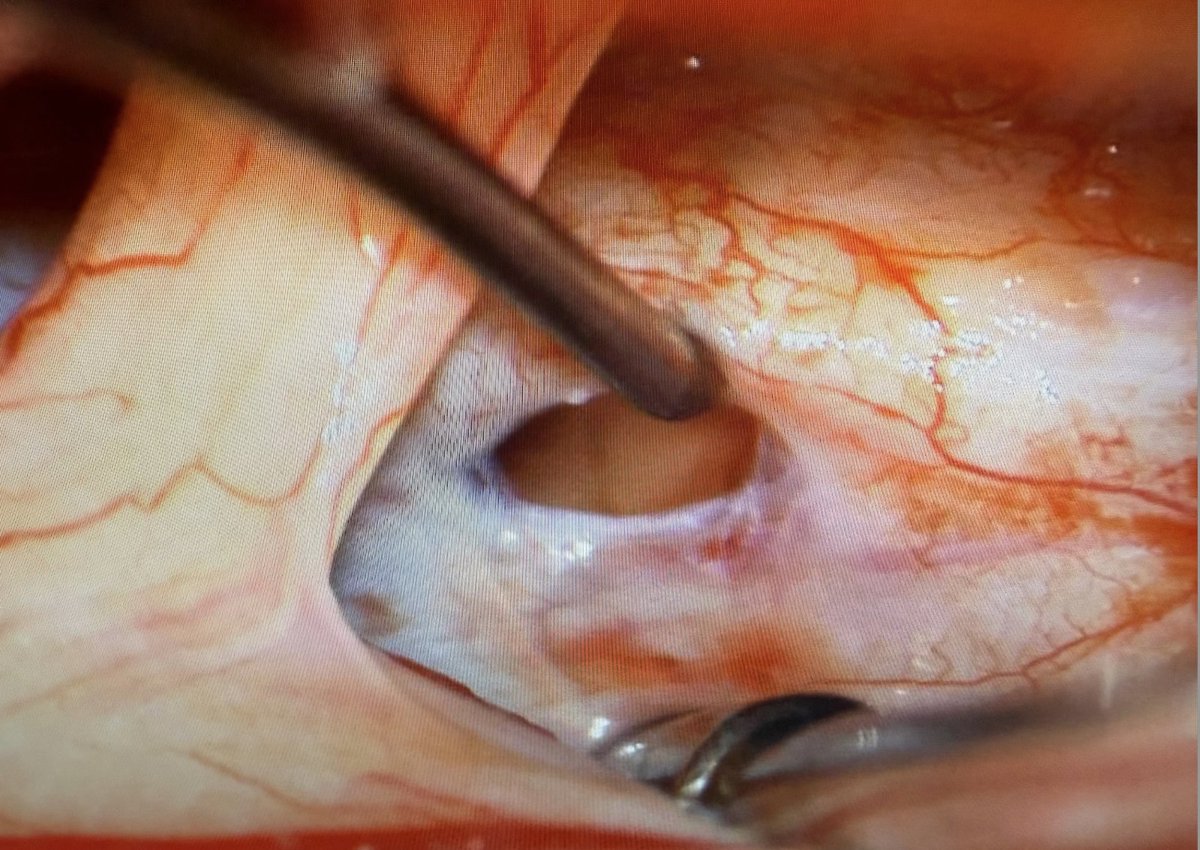

Spinal CSF-venous fistulas almost always arise from meningeal diverticula. The diverticular size can vary from tiny (submillimeter) to massive (think dural ectasia). At least one-third of diverticula change size when a fistula forms @spinalCSFleak pubmed.ncbi.nlm.nih.gov/41730631/